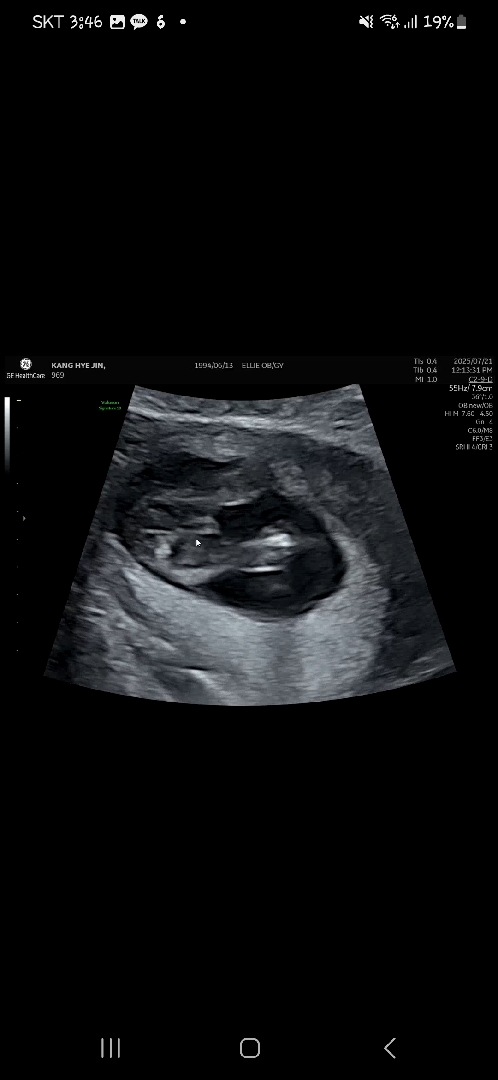

13주6일 ~남자일까요..?아들맘님들 도와주세요!

아직 확실치 않다하시는데, 첫째가 여자아이여서 , 초음파보고 어?남자예요?이랫더니 웃으시더라구요!! 거의남자일까용..?

확실하진않지만 여자같은데요? ㅜ